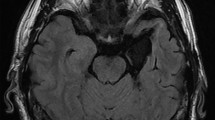

Therefore, the present study explores the time- and laterality-specific contributions of the mTL to the emotion-sensitive ERP components, P1, N1, early posterior negativity (EPN), and late positive potential (LPP)4,18,19,33,34,35, as well as to oscillatory GBA32,36,37,38,39. ERPs and GBA are complimentary and temporally highly resolved neural signatures of emotional face processing. We derived these markers from a comparatively large and well characterized sample of patients with unilateral temporal lobe resections (18 lTLR and 18 rTLR, Fig. 1) and a case-matched healthy control group (HC). Participants were presented with a series of fearful and neutral facial expressions. Building on previous research19, we expected that rTLR patients would exhibit reduced emotion differentiation in early ERP components. Given the sparse data on emotion differentiation in lTLR patients, we did not formulate directional a priori hypotheses for this group. Nevertheless, based on previous findings of altered fear processing in individuals with left-hemispheric amygdala lesions18, we anticipated that their responses would deviate from the overall group mean. Our primary focus is on electrophysiology data, but we also assessed subjective stimulus appraisal and recognition memory for faces in the three groups of participants.

Overlap of temporal lobe resections, which consisted of anteromedial (including the hippocampus, n = 13) and apical (hippocampus sparing, n = 5) temporal lobe resections in the lTLR patients (top row) and exclusively of anteromedial temporal lobe resections (n = 18) in all rTLR patients (n = 18, bottom row). Images are centered at the mean overlap maxima of the resections. Abbreviations: lTLR left temporal lobe resection, rTLR right temporal lobe resection.

For all patients, temporal lobe resections included the amygdala and surrounding tissue as well as the hippocampus (anteromedial temporal lobe resection). In five lTLR patients, the hippocampus was spared (apical resection). Figure 1 shows the resection extents and their overlap. Patients were surgically treated at the Department of Epileptology (Krankenhaus Mara) of Bielefeld University for pharmacoresistant temporal lobe epilepsy. Testing was done at least 24 months after surgery to ensure sufficient post-operative adjustment in all patients. No patients had amygdala lesions prior to the surgery, as identified from structural imaging and post-operative histology. Patients’ surgery outcome was classified according to criteria proposed by Engel80. Thirty patients were free of disabling seizures (Engel I), two patients reported rare disabling seizures (Engel II), and four had less favorable outcomes (Engel III & IV). Eighteen patients (9 rTLR, 9 lTLR) confirmed to use anti-seizure medication at the time of testing. Participants gave written informed consent according to the Declaration of Helsinki and received a monetary reward of 100 Euros for their participation in the entire study, which consisted of EEG, fMRI, and extensive neuropsychological testing. fMRI and neuropsychology data are reported elsewhere8,81. The study was approved by the ethics committee of the German Psychological Association (DGPs). All ethical regulations relevant to human research participants were followed.